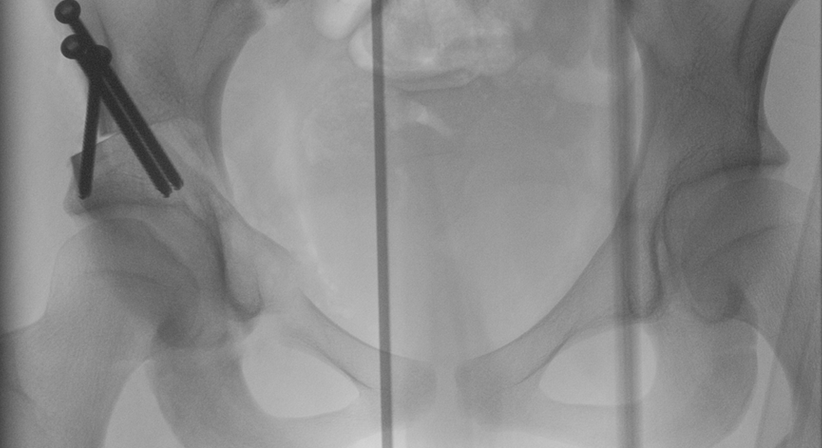

Ich führe seit vielen Jahren die minimal invasive PAO (periazetabuläre Osteotomie) durch, die von meinem Lehrer, dem Dänen Prof. Kjeld Sobale entwickelt wurde. 2021 habe ich diese Technik aus Deutschland in die Steiermark mitgebracht.

Der Vorteil dieser Technik ist, dass die Patienten sehr schnell genesen und bereits nach wenigen Tagen wieder die Klinik verlassen können. Sie können ab dem ersten Tag normal sitzen und haben lediglich eine 6-wöchige Teilbelastung (mit den älteren Techniken war meist eine 3-monatige Teilbelastung nötig). Nach heutigem Kenntnisstand können mit der minimal invasiven PAO gelenkersatzpflichtige Arthrosen mehrere Jahrzehnte hinausgeschoben werden. Allerdings muss sehr früh therapiert werden.